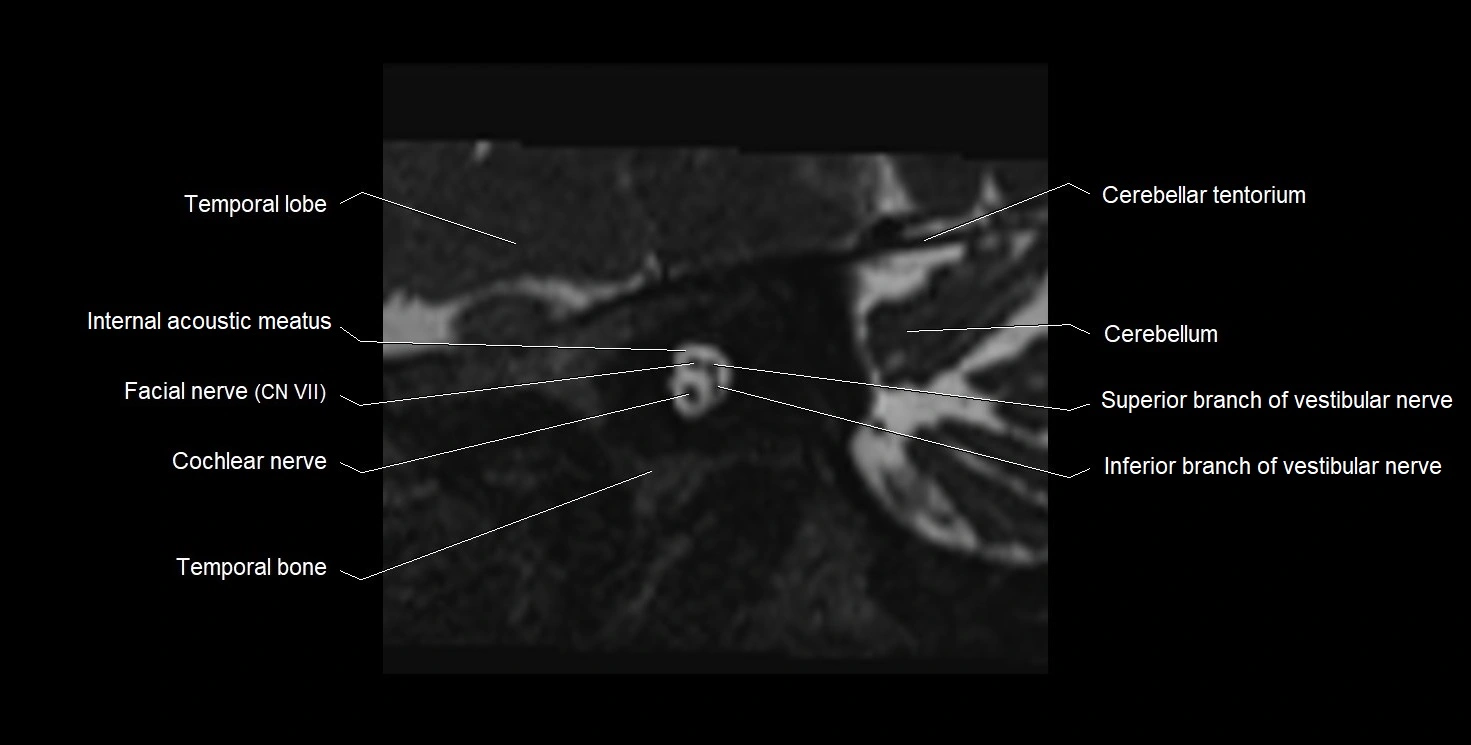

MRI images

image